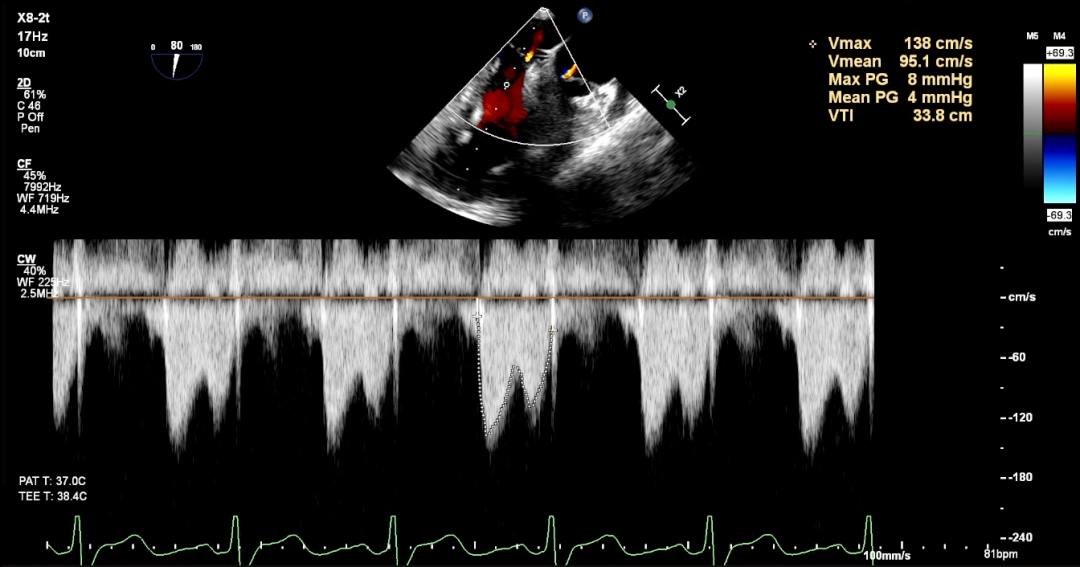

随后将可操控导引导管(SGC)及二尖瓣夹输送系统(CDS)送入左心房。仔细调整XTW二尖瓣夹的轨迹和方向后,进行首次夹合,超声提示仍存在少量二尖瓣反流,考虑为后侧瓣叶捕获不足所致,且侧边瓣叶仍存在明显脱垂。遂打开夹臂,在左心房内调整夹子位置,向后侧、外侧移动,以捕获更多后侧瓣叶,再次夹合,成功解决反流与脱垂问题,测得术后平均压差为4mmHg,手术圆满成功。

术后平均压差为4mmHg